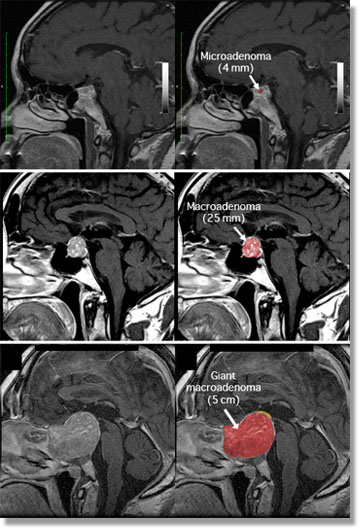

The bean-sized Pituitary gland or "master gland" is extremely important in regulating the function of many other glands and organs of the body . It lies behind and between the eyes at the base of the brain, just beneath the hypothalamus to which it is connected by a thin stalk.

Non-functioning or non-secreting tumors are characteristically slow-growing. If they are not compressing the visual nerves, such tumors are often merely observed.Microsurgery is commonly used to treat a non-functioning tumor. The neurosurgeon may use the transsphenoidal route at the base of the cranium or a craniotomy (removal of part of the skull).

In selected cases, Gamma Knife Radiosurgery has the advantage of delivering a high dose of radiation in a single fraction while minimizing the risk of damage to the nearby visual nerves and normal pituitary gland. Also, Gamma Knife offers the convenience of a single treatment compared to several weeks of fractionated radiation therapy. Gamma Knife radiosurgery can be utilized as either the primary or secondary treatment for pituitary tumors.

Patients with functioning or homone-secreting tumors generally require immediate relief of their symptoms, which may include hypertension and diabetes. Microsurgery is usually used as the primary treatment.

When a functioning tumor is incompletely removed or recurs, further treatment is imperative to try to stop excess hormone secretion. In these cases, the residual tumor is usually small and can often be visualized on an MRI. Gamma Knife radiosrugery is ideally suited for this type of situation